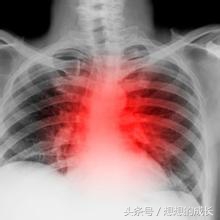

新生儿肺炎

新生儿肺炎是新生儿时期最常见的呼吸道感染病,很容易引起呼吸衰竭、心力衰竭、败血症乃至死亡,一定不能掉以轻心。

新生儿肺炎的早期症状主要为:口周发紫、口吐泡沫、呼吸快、鼻翼扇动、食欲不振、容易呛奶、精神萎靡、烦躁不安、哆嗦、腹泻等。

重度肺炎的主要症状为:呼吸急促(每分钟可达80次以上),鼻翼扇动,有三凹症(吸气时孩子的胸骨上窝,肋间隙和剑突下出现凹陷),呼气时*吟呻**、脸及四肢末端明显发紫、面色苍白或青灰、呼吸不规则甚至暂停呼吸、两肺有密集的细湿啰音。